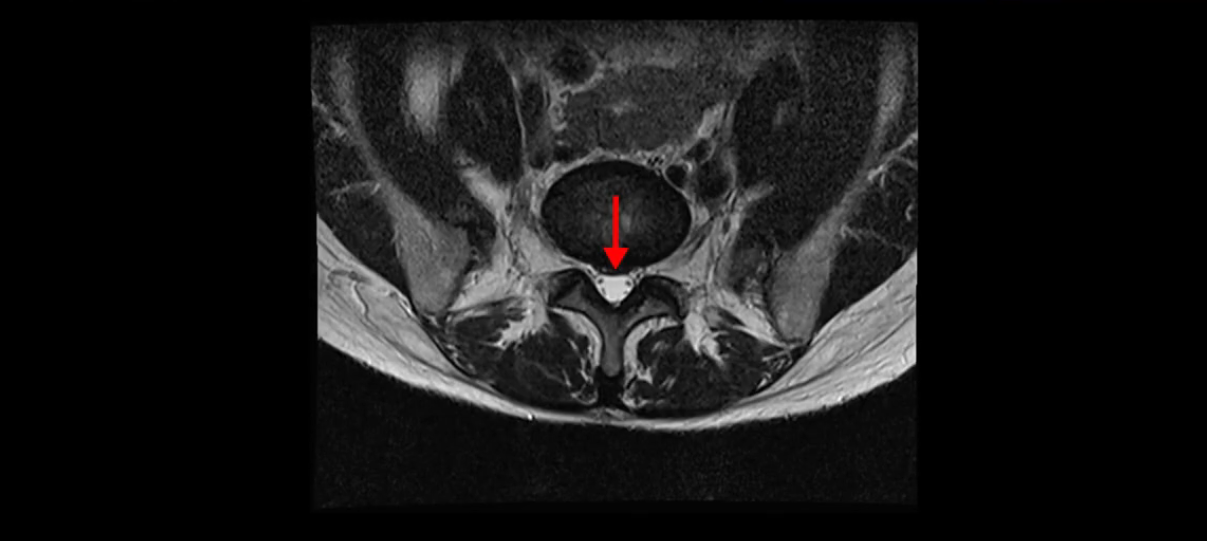

이분 MRI를 보시면 두 마디의 퇴행성디스크가 있습니다. 그리고 디스크가 조금씩 밀려 나와 있고요. 그런데 디스크 탈출 정도는 두 마디 다 심하지 않습니다. 4번 5번에는 디스크 탈출이 약간 있고,

척추관협착도 약간 진행이 되고 있고요.

5번 1번은 디스크 탈출이 가운데 쪽으로 살짝 있습니다.

또한 양쪽 신경 가지가 빠져나가는 추간공은 매우 넓은 상태입니다.

중요한 것은 이 정도 경미한 탈출과 협착으로는 양쪽 다리가 저리고 아플 수가 없습니다.

그리고 만약에 이 디스크가 급성으로 찢어진 것이라면 아주 심한 디스크성 통증이 있겠죠. 기침이나 재채기를 하면 심하게 아프고 허리를 조금만 구부려도 아주 날카로운 통증들이 생길 겁니다. 그런데 이분은 이런 증상이 전혀 아닙니다. 디스크의 돌출 정도와 협착이 전혀 심하지 않기 때문에 이분이 가지고 계신 양쪽 다리 저림, 특히 이분은 누워있을 때도 양쪽 다리가 저리다고 하는데, 디스크 때문에 그런 증상은 생길 수가 없습니다. 또 이 디스크는 오래된 디스크, 이미 찢어진 섬유륜이 아문 디스크이고, 그러니까 이분은 기침이나 재채기를 못하는 증상이 없는 거죠. 그 다음에 허리를 구부릴 때 뻐근한 증상은 있지만 아주 날카로운 통증은 없습니다.

이분 MRI를 보시면 퇴행성디스크가 있고 약간의 협착이 있지만 이 정도의 퇴행성디스크와 협착으로는 신경이 눌려서 양쪽 다리가 저리고 아픈 증상이 나올 수가 없습니다. 그래서 MRI와 이 환자분의 다리 증상이 매치가 안 된다고 하는 의사들이 많은 겁니다.